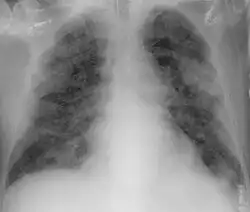

Imaging

Chest CT scans may be helpful to diagnose COVID‑19 in individuals with a high clinical suspicion of infection but are not recommended for routine screening.[175][187] Bilateral multilobar ground-glass opacities with a peripheral, asymmetric, and posterior distribution are common in early infection.[175][188] Subpleural dominance, crazy paving (lobular septal thickening with variable alveolar filling), and consolidation may appear as the disease progresses.[175][189] Characteristic imaging features on chest radiographs and computed tomography (CT) of people who are symptomatic include asymmetric peripheral ground-glass opacities without pleural effusions.[190]

Many groups have created COVID‑19 datasets that include imagery such as the Italian Radiological Society which has compiled an international online database of imaging findings for confirmed cases.[191] Due to overlap with other infections such as adenovirus, imaging without confirmation by rRT-PCR is of limited specificity in identifying COVID‑19.[190] A large study in China compared chest CT results to PCR and demonstrated that though imaging is less specific for the infection, it is faster and more sensitive.[174]